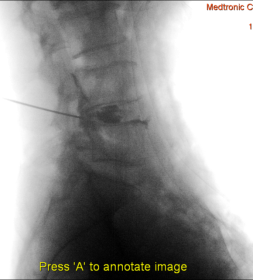

(1)患者采用俯卧位,提前设置好O型臂多维外科成像系统所需扫描定位平面(图1,图2),在正位透视下标定一条腰椎棘突中线,再沿髂棘最高点做一水平线,腰5骶1椎间盘正侧位的透视交叉点,即为穿刺点,一般在中心线旁开10-12cm左右处选一穿刺点。此线为穿刺的方向和角度(图3)。

图2 定位椎间隙 侧位

图3 穿刺方向